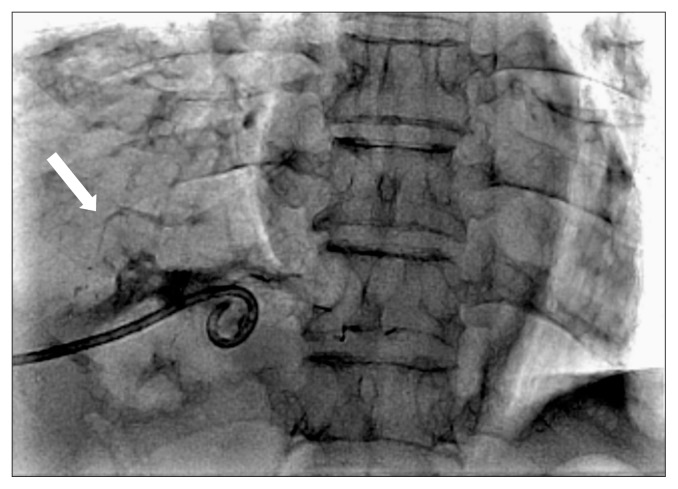

支气管胆道瘘是一种罕见的疾病,定义为胆道和支气管树之间的异常连接。我们报告成功的手术修复支气管胆管瘘。一位78岁的男性接受了手术和几轮经导管动脉化疗栓塞和射频消融治疗肝细胞癌。患者痰液呈绿色,慢性咳嗽数月,经内镜治疗后症状未缓解。我们在开腹和开胸的情况下行右下叶肺叶切除术和网膜固定术治疗支气管胆管瘘。成功闭合支气管胆管瘘,术后胆液消失。

Bronchobiliary fistula is a rare disease defined as an abnormal connection between the biliary tract and the bronchial tree. We report the successful surgical repair of bronchobiliary fistula. A 78-year-old man underwent surgery and several rounds of transcatheter arterial chemoembolization and radiofrequency ablation as treatment for hepatocellular carcinoma. He presented with greenish sputum and chronic cough for several months, and his symptoms did not resolve after endoscopic treatment. We performed lobectomy of the right lower lobe and omentopexy for bronchobiliary fistula under laparotomy and thoracotomy. The bronchobiliary fistula was successfully closed, and the bilious sputum disappeared after surgery.